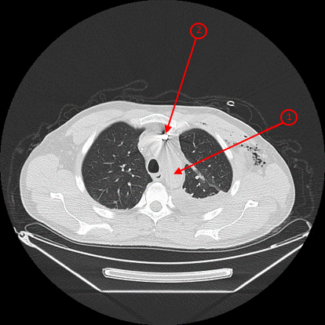

В ходе обследования и лечения в ГВКГ им.Н.Н.Бурденко у больного выявили постдиафрагмальный абсцесс и провели проточно-аспирационное дренирование, на фоне которого абсцесс разрешился. В ходе обследования по R-графии у больного были выявлены множественные инородные тела (осколки) в мягких тканях (Рисунок 1), но особое внимание на себя обращал осколок, который находился на дуге аорты.